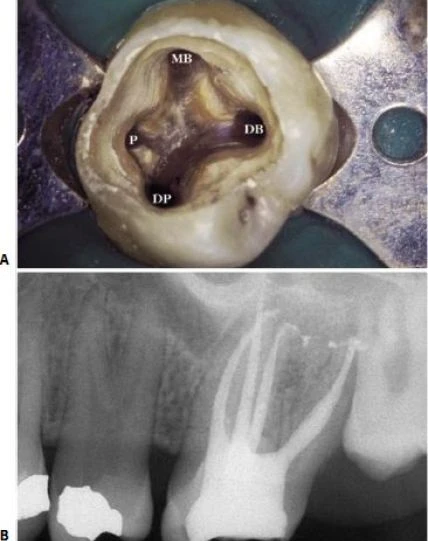

Hình 11.57. A. Xoang tủy của răng #26 với hai ống trong ở hai chân răng. Lưu ý P: palatal canal (ống trong); MB: mesiobuccal canal (ống ngoài gần); DB: distobuccal canal (ống ngoài xa); DP: distopalatal canal (ống xa trong). B. Phim sau điều trị trên cùng răng này.